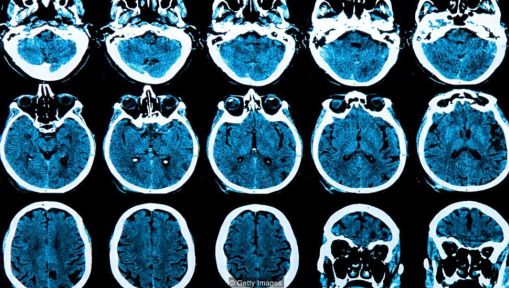

N 神经网络(Neural Networks)

为了创造能像人一样思考的机器,计算机科学家们转向自然界来解决这个问题,创造了模仿大脑结构的算法,这是可以理解的。为了做到这一点,他们正在创建算法网络,这些算法被设计为像大脑中的神经元一样工作。当机器学习时,这些数学神经元之间的连接变形成集群。

全世界的医生都在越来越多的使用AI软件来检测癌症或眼部疾病的早期症状,但是最新研究成果表明,人工智能还能在一个人出现任何病兆之前的好几年,就预测到他是否会患上像阿尔茨海默病这样的疾病。